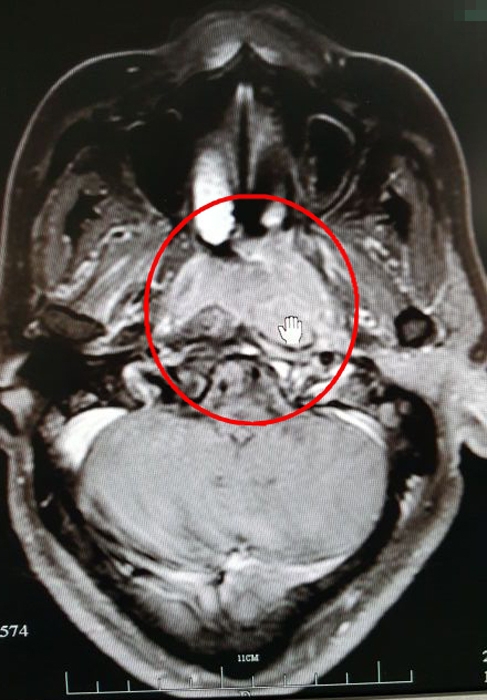

放療前的CT影像(紅圈處為病灶)

放療后的CT影像(紅圈處為病灶)

??? 目前,吳大姐鼻咽部的腫塊已經(jīng)明顯消失,治療效果明顯。